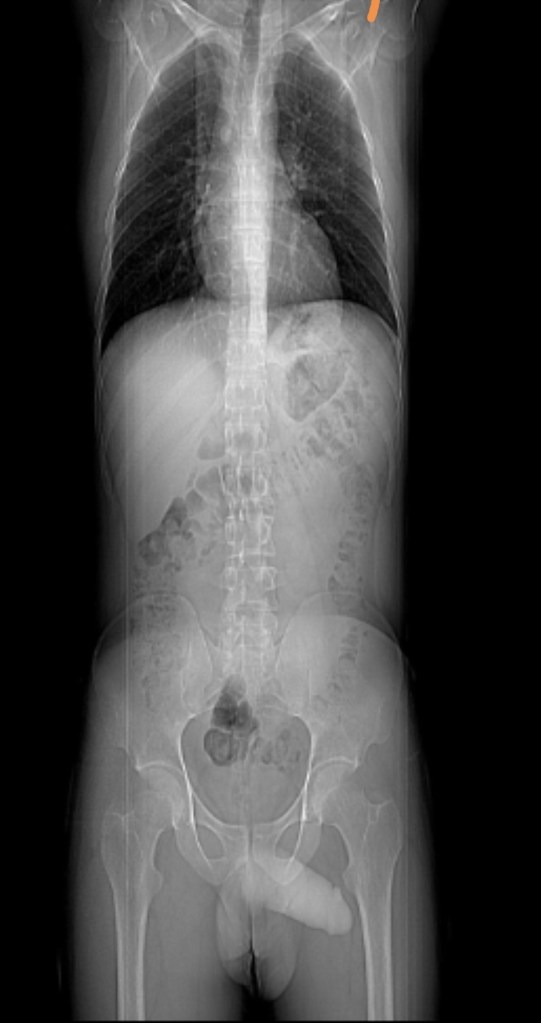

When I asked Google if, in an X-Ray of a hip and pelvis, the penis and testicles could be seen, it answered no. When I scrolled down, I saw about 400 comments stating otherwise. With pictures to prove it.

Now, to give Google some credit, it’s official answer was: “No, a standard X-ray of the hip and pelvis will not typically show the penis and testicles clearly, as they are soft tissues that are largely obscured by the surrounding bone structure; however, in some cases, with specific positioning and if the patient is very thin, faint outlines of the male genitalia might be visible on the image, but this is not reliable or intended for diagnosis.”

From Wikipedia: “The John Thomas sign, also known as the Throckmorton sign, is a slang or joke term used in the field of radiology. It refers to the position of a penis as it relates to pathology on an X-ray of a pelvis. When the penis (visible on the X-ray as a shadow) points towards the same side as a unilateral medical condition such as a broken bone, this is considered a ‘positive John Thomas sign,’ and if the shadow points to the other side, it is a ‘negative John Thomas sign.’”